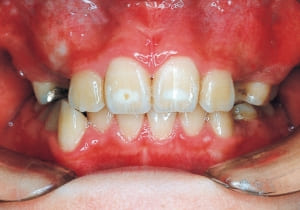

2 After Phase 2 Treatment 6-6-’94

This was a case of significant Protruding upper bite, and early treatment was deemed necessary from a functional perspective.

Although the treatment spanned a long period of 8.5 years from the initial visit to the removal of the retainer, such a treatment duration is required when initiating treatment early. This case raised numerous issues, including whether to utilize growth for treatment and determining the optimal timing for treatment initiation.